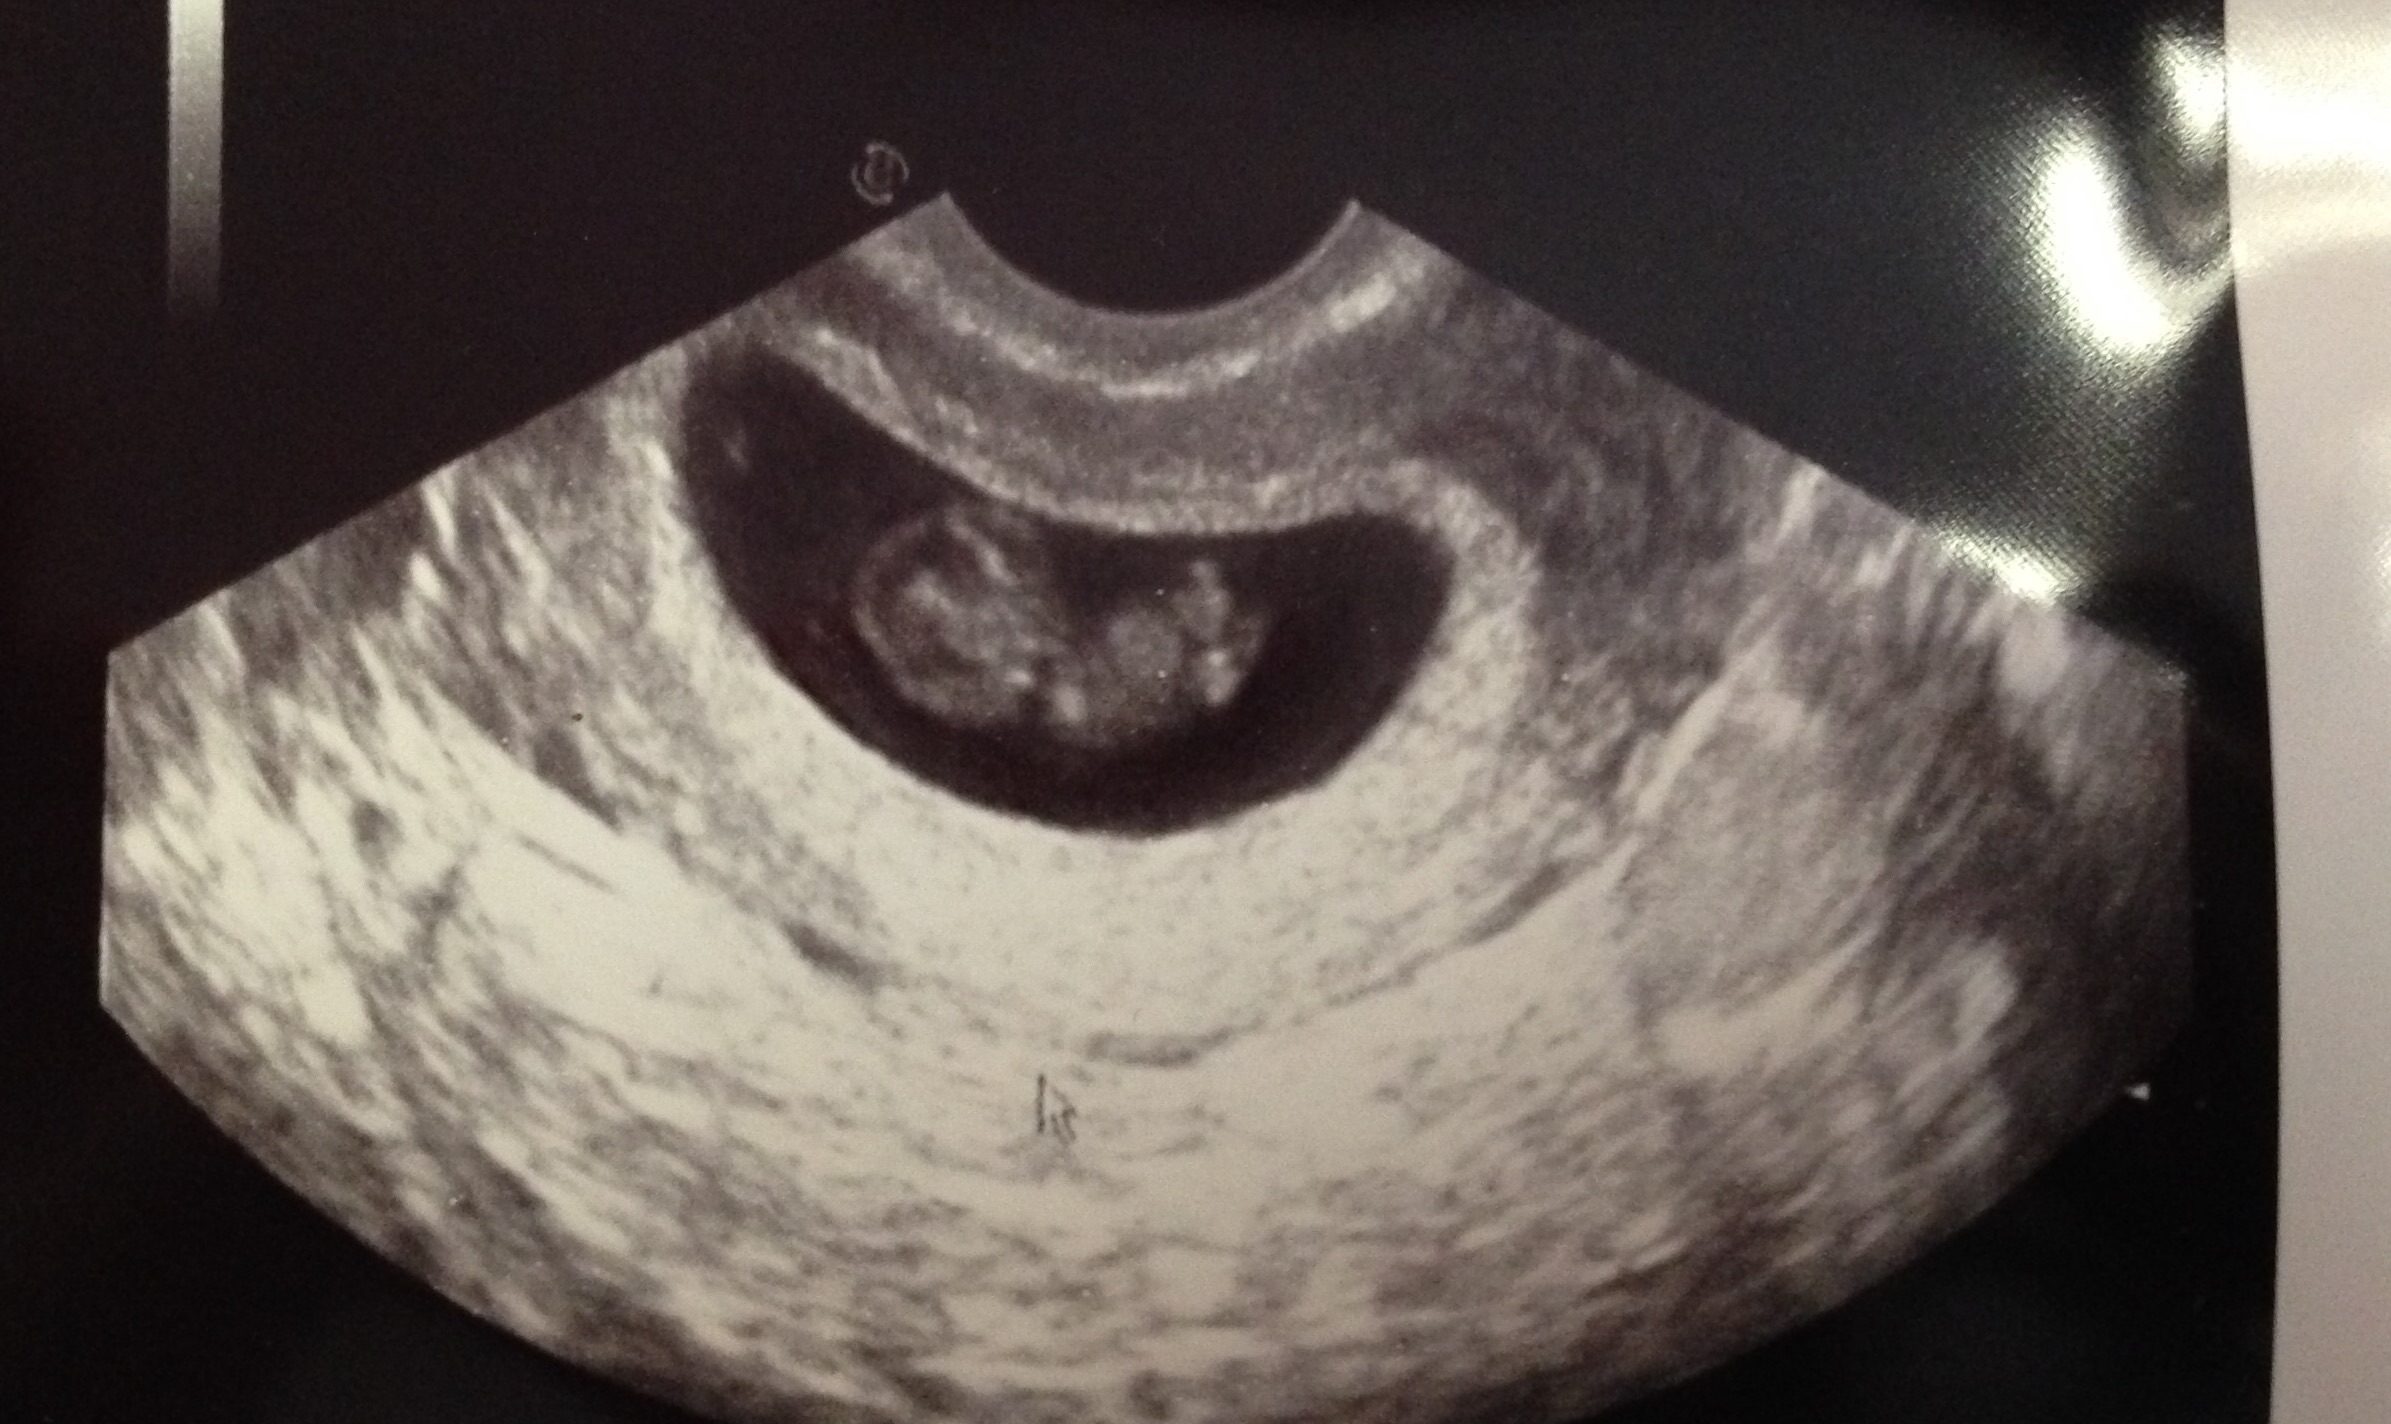

first appointment went amazing! Got to hear the heart beat of my little one and it was wiggling all over the place! Heartbeat was 166 and doc said everything looks super healthy and right on track!!! I am beyond excited!! Hubby couldn't stop looking at the ultrasound pics on the car ride home :)

• Wow, great ultrasound pic! Mine from 7 weeks just looks like a blob lol. Hopefully I'll get a more human looking one at my appointment tomorrow! :)